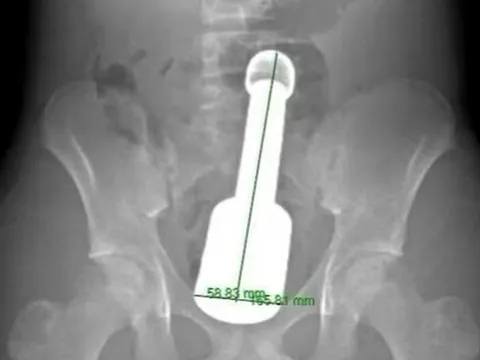

Ảnh minh họa.